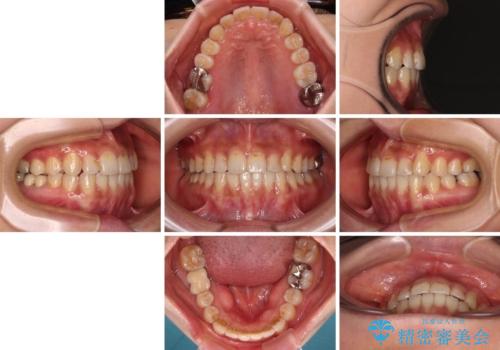

- 上下のクロスバイトと前歯のデコボコを気にして来院された患者様です。

骨格的に下顎がやや前方にあり、奥歯にクラウンが装着されているため、矯正治療後半の不安定な咬み合わせを避けるのであればワイヤー矯正がおすすめとなりますが、希望によりインビザラインにて治療を行うこととしました。

インビザラインを用い、IPR(歯と歯の間を削る)と歯列全体を拡大させることで、歯並びを整えていくこととしました。

懸念されたとおり、右下のクラウン部分が全く咬み合わず、仕上げの段階で治療期間が長くなりました。